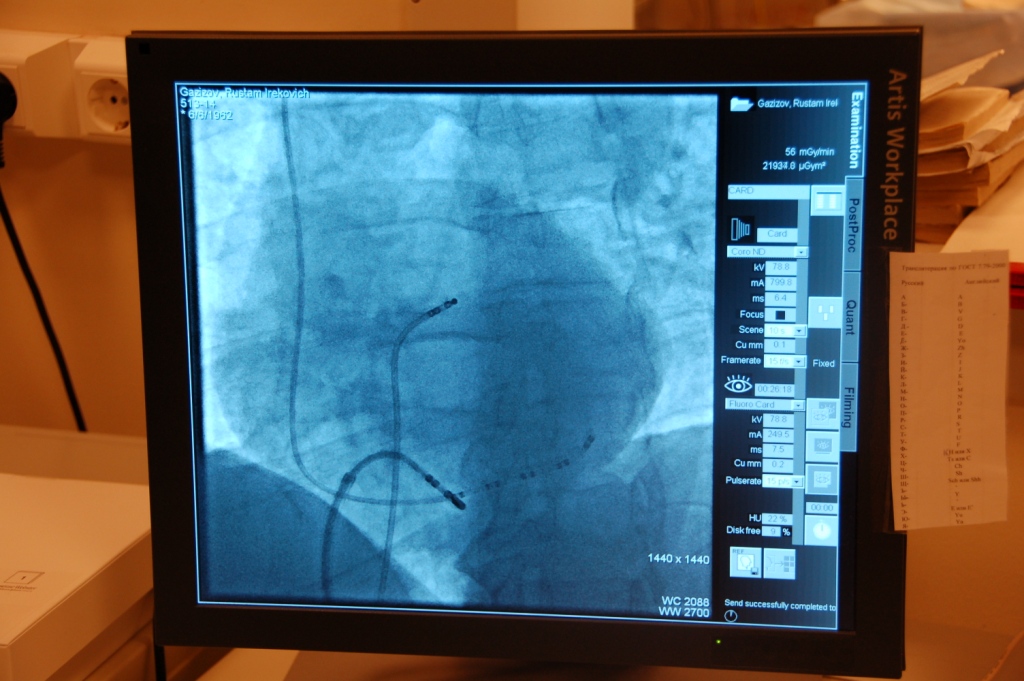

Хирургическое лечение нарушений ритма сердца включает в себя проведение инвазивного электрофизиологического исследования и операции радиочастотной аблации (ЭФИ РЧА). Все вмешательства проводятся в условиях рентгенохирургической операционной, под местным обезболиванием, без наркоза и разрезов, доступ проводится посредством пункции сосудов, безболезненно. При успешном оперативном вмешательстве излечение происходит уже на операционном столе и через несколько дней пациент выписывается домой.